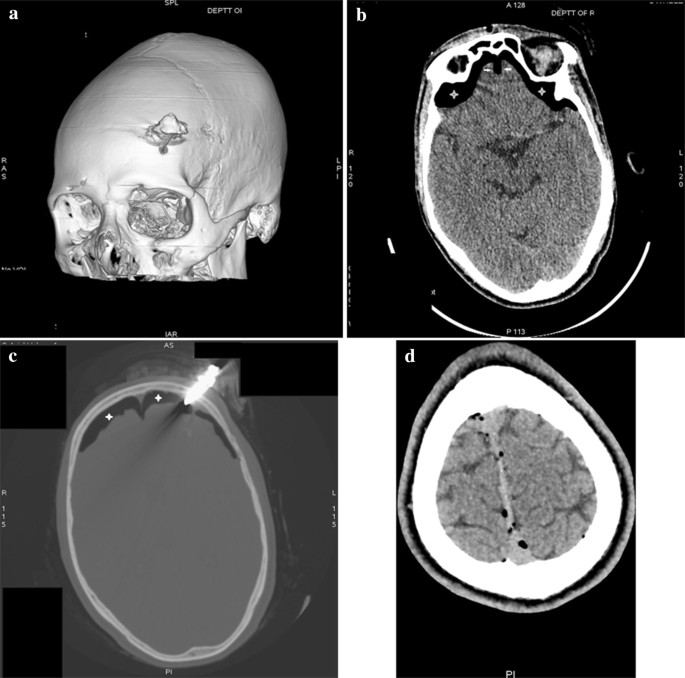

Traumatic Tension Pneumocephalus Two Cases And Comprehensive Review Of Literature

Post Traumatic Unilateral Tension Pneumocephalus Eurorad